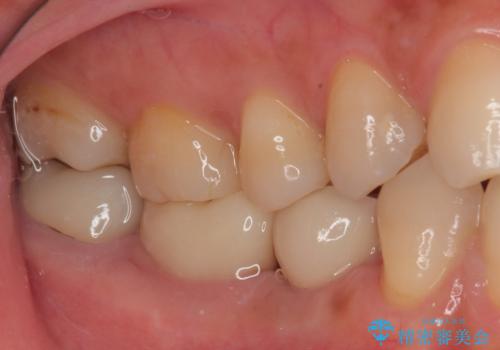

インプラント治療をきっかけに、銀歯を全てセラミックに替えていきました。

人の目を気にせずに、大きく口を開けて笑えるようになりました。